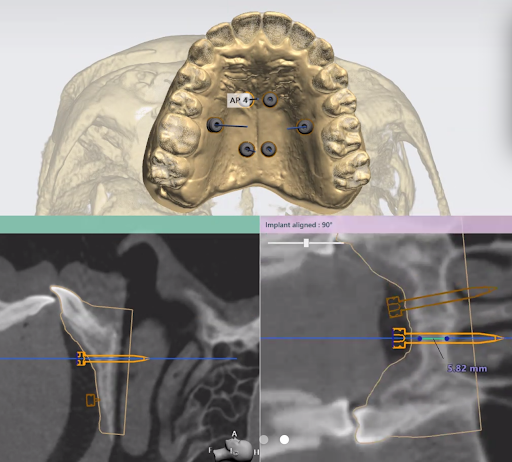

2. Custom Digital Planning

Every MARPE appliance is custom-designed using advanced digital planning. We determine ideal placement, expansion goals, and biomechanics—tailored specifically to each patient.

Each case is designed by the doctor with the leading laboratory manufacturing Custom MARPE’s.